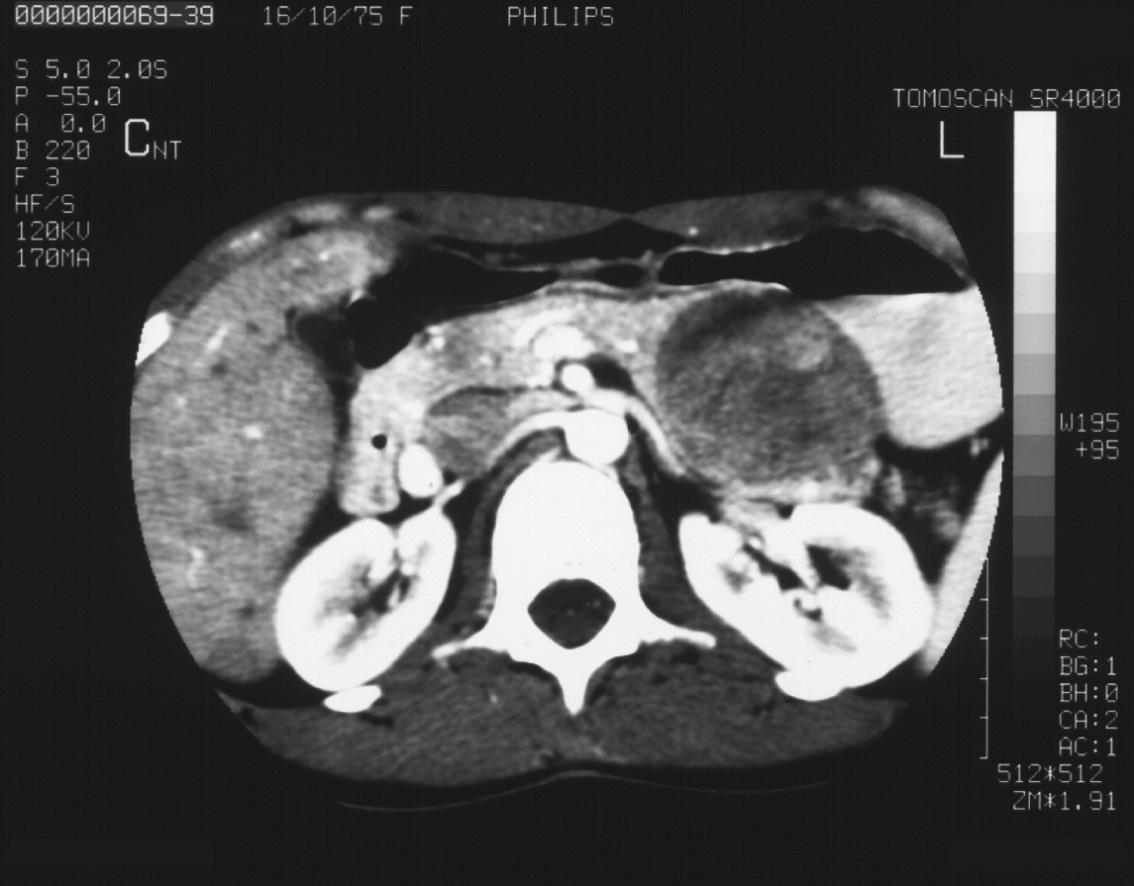

14.5. Spleen

14.5.1. Anatomy

Its diameter measured in the spleen hilum is normal until 45 mm, in case of larger diameter minor, moderate or extensive splenomegaly can be noted (Figure 46).

Figure 46: Splenomegaly, contrast enhanced CT

CT imaging:

By the performance of native and contrast-enhanced CT, the determination of possible circumscribed splenic parenchymal lesions is relevant besides those lesions described above by the radiograph and US examinations (calcifications, accessory spleen). The adjudication of splenic dimensions can be more accurate by CT compared to US.

An important artefact concerning the spleen after contrast administration is the so-called „tiger” spleen, which is not a real pathologic finding but a very inhomogeneous bizarre contrast uptaking splenic parenchyma in the arterial phase.